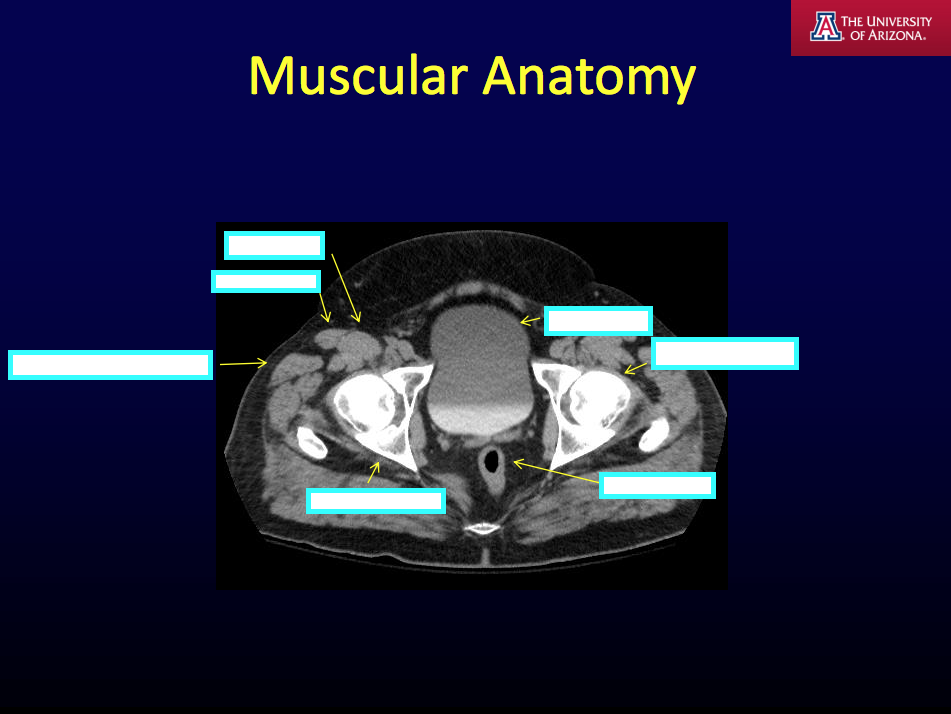

CT